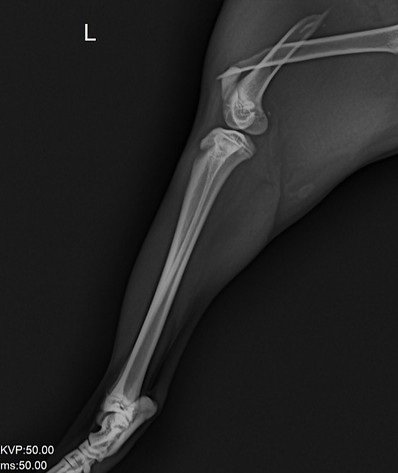

Imagen 2. FRACTURA COMPLETA OBLICUA DEL TERCIO DISTAL DEL HÚMERO VISTA L.M. (Latero-Medial).

1. Costillas

2. Esternón

3. Escápula

4. Tubérculo supra glenoideo

5. Tubérculo mayor

6. Fractura

7. Húmero

8. Tuberosidad del olécranon

9. Radio

Fuente: Kanicat